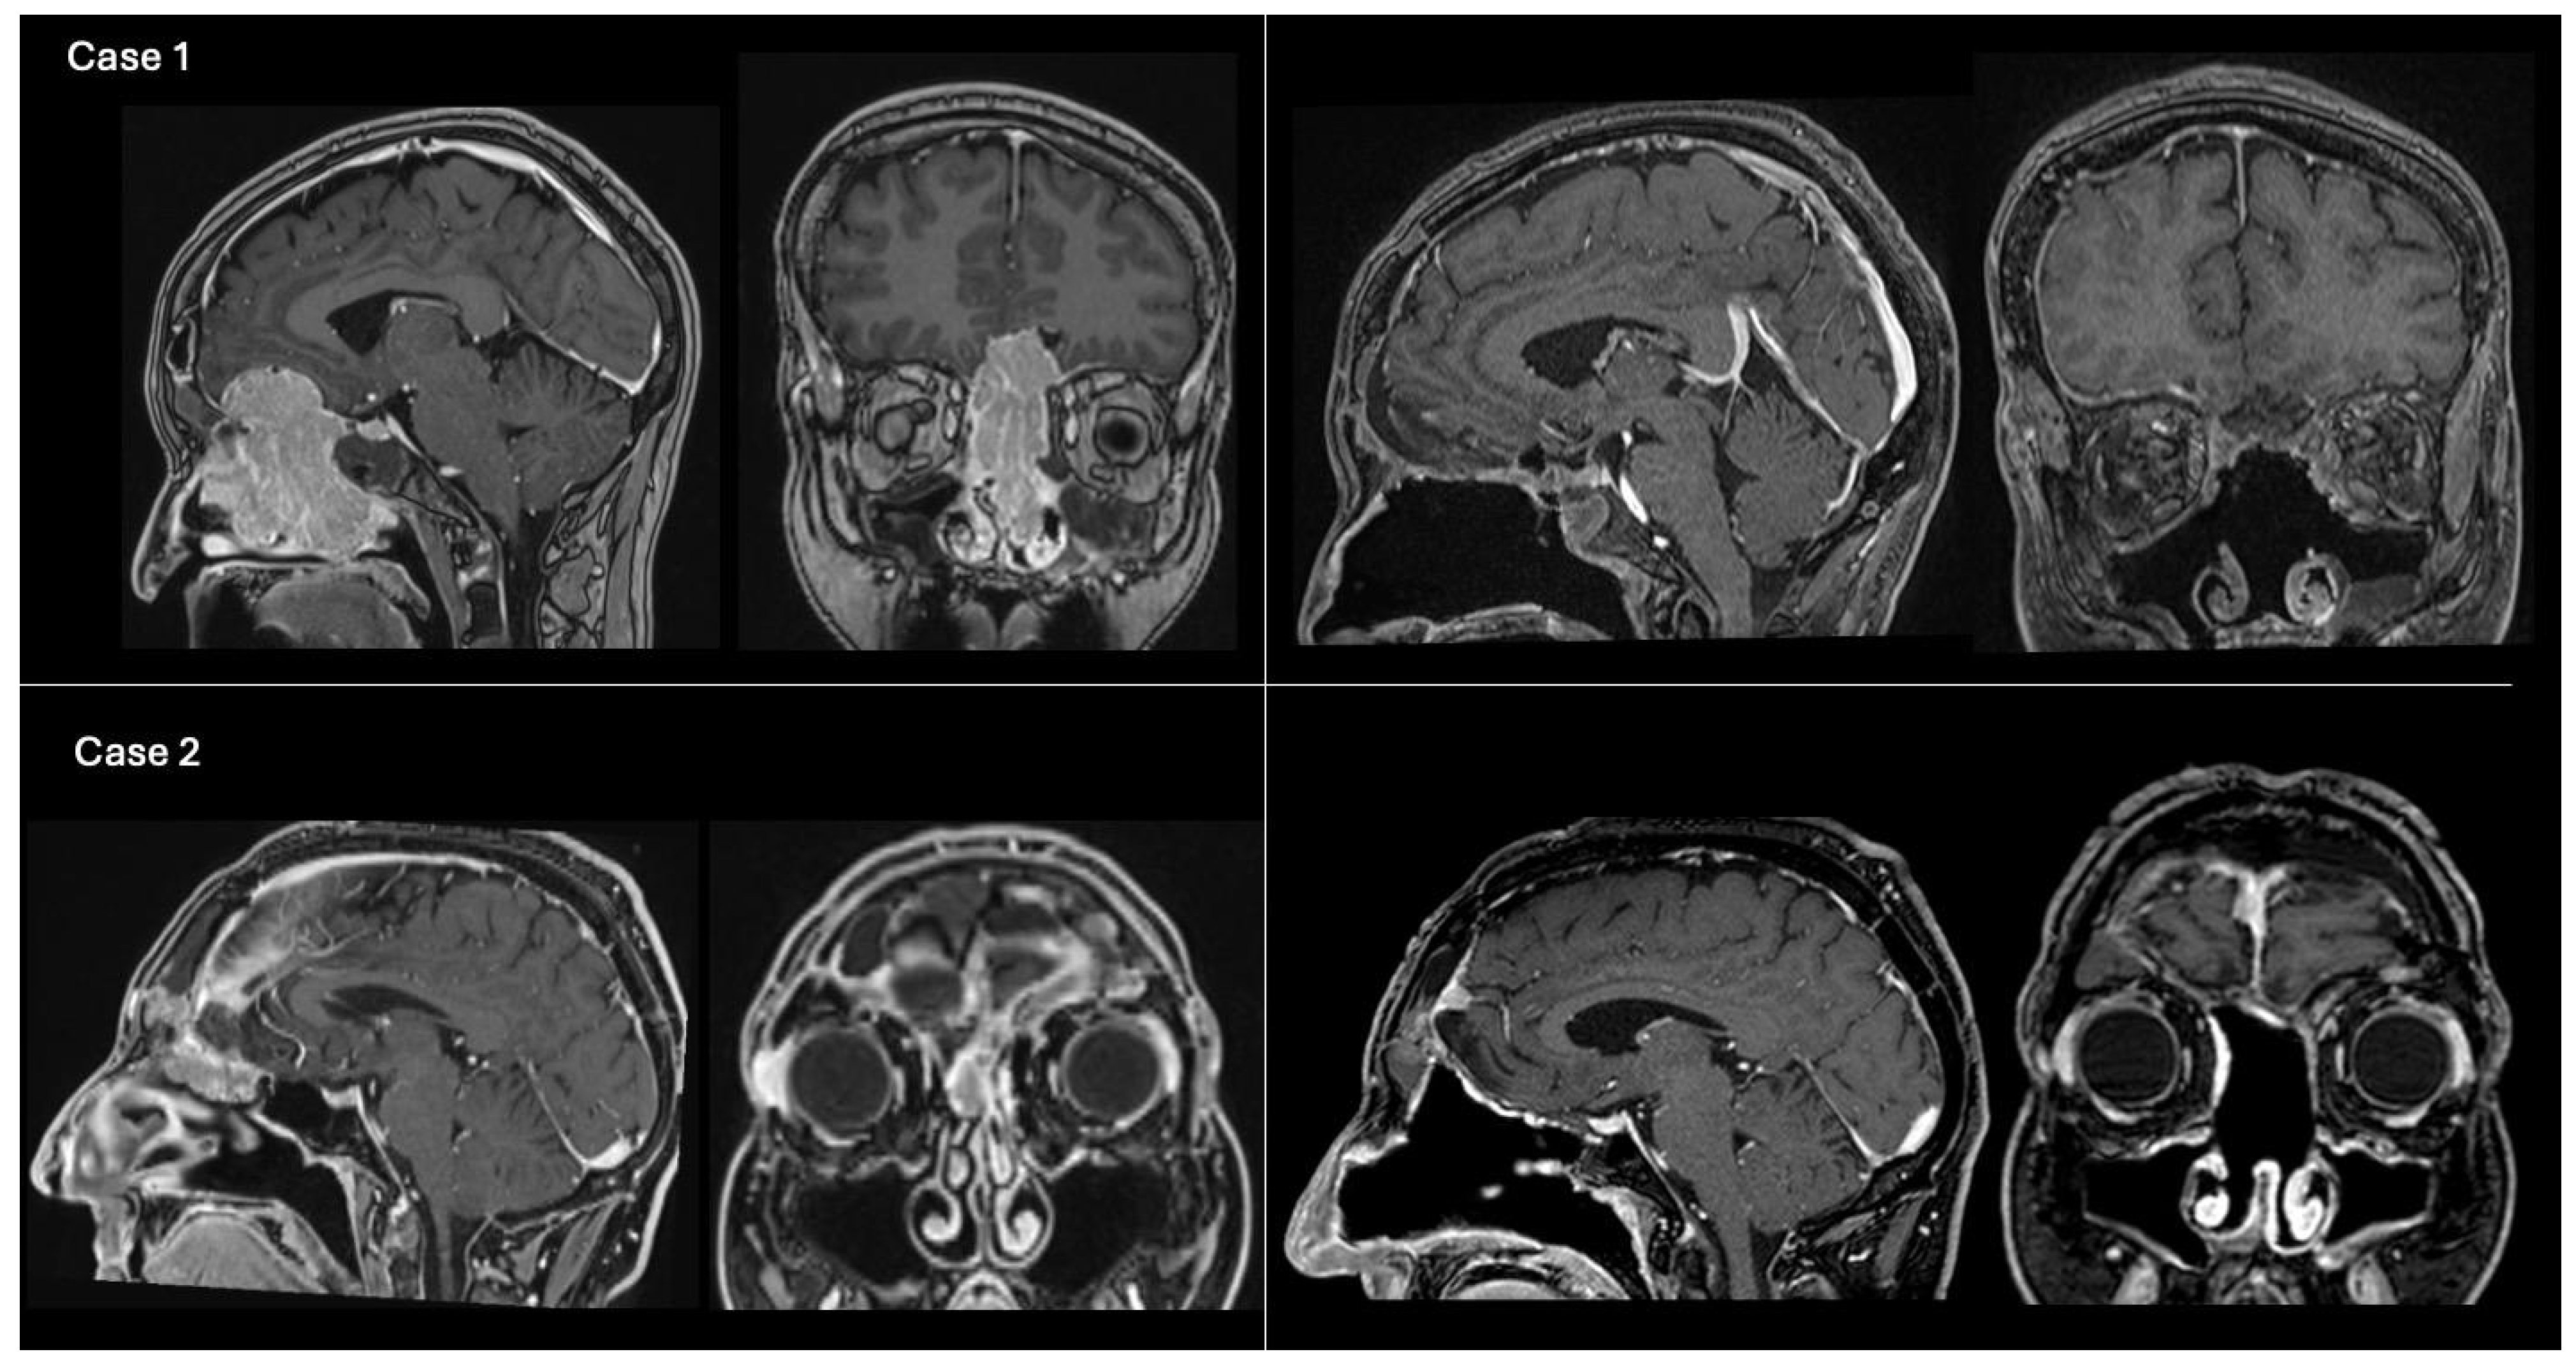

Figure 2. Example cases of preoperative and postoperative T1-weighted contrast-enhanced brain MRI. Case 1 (above): On the left, preoperative MRI on sagittal and coronal views showing an olfactory neuroblastoma (grade C, modified Kadish classification [15]) invading the anterior cranial fossa. The ASB was reconstructed using method 1 (pericranial flap + overlay fascia lata graft). The NSF was not available due to tumor invasion of the nasal septum mucosa. On the right, 1-month postoperative MRI showing gross total resection of the tumor. Case 2 (below): On the left, preoperative MRI on sagittal and coronal views depicting a recurrent ASB atypical meningioma (Grade 2, WHO 2021), previously operated via open approach, with unilateral extension into the right nasal fossa. The ASB was reconstructed using method 2 (pericranial flap + fascia lata graft + NSF). On the right, 2-year postoperative MRI in sagittal and coronal views, demonstrating total tumor removal and intact ASB reconstruction following adjuvant RT.